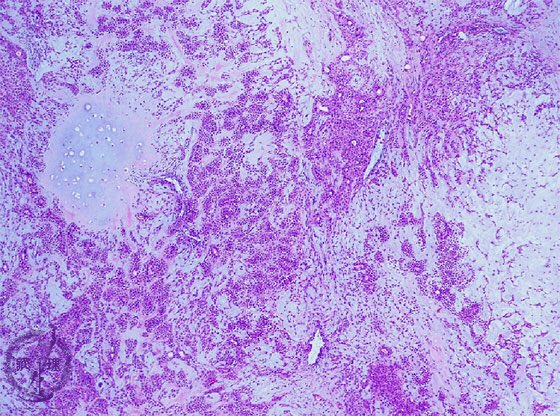

病理コア画像 144486-病理コア画像 肝硬変

病理コア画像 肝硬変

10 肝臓 1 ウイルス性肝炎 肝硬変 病理コア画像